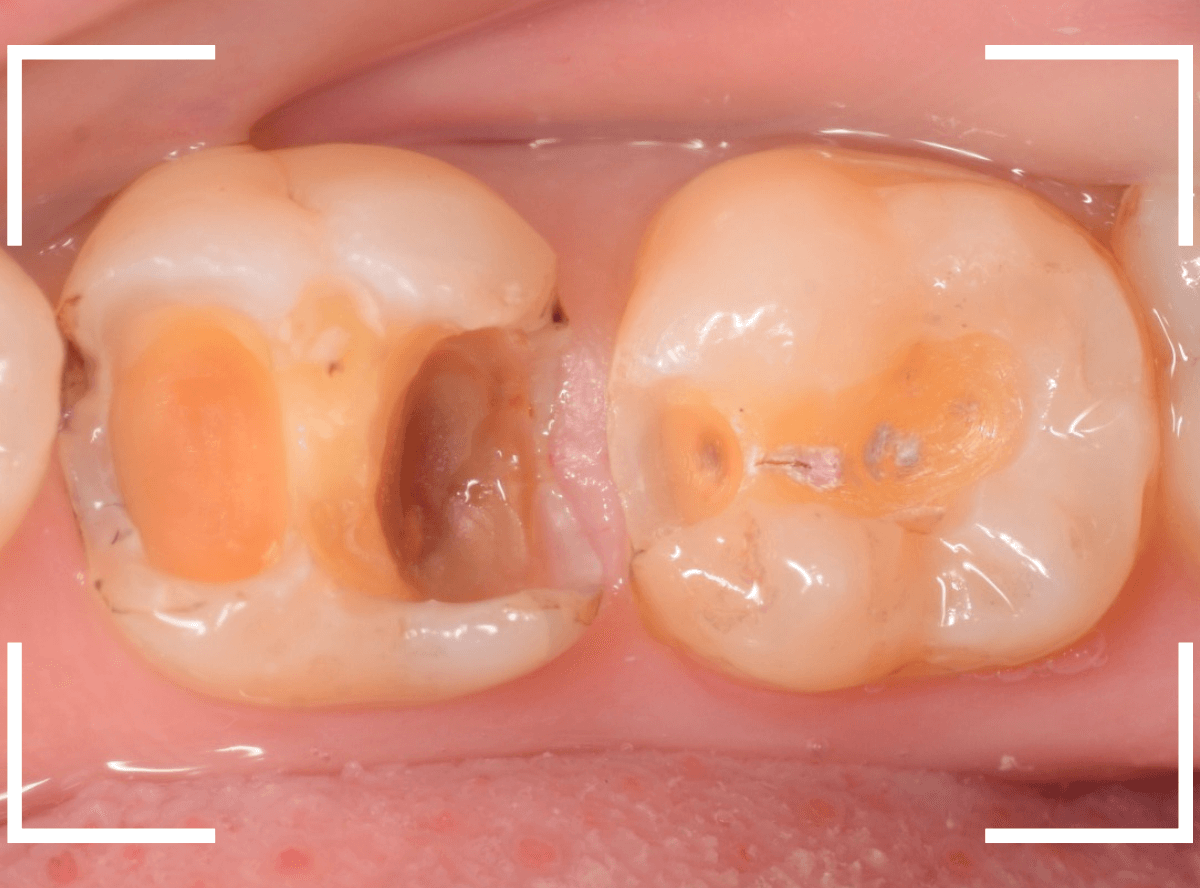

まずは、奥のメタル・クラウンを外します。

メタル・コアが入っていますが、こちらも慎重に外して、中を調べていきます。

レントゲン写真では問題なさそうでしたが、メタルコアを除去すると、中は真っ黒でした。

このように、コアの中で虫歯が進行している場合もありますので、さし歯をやり直す際は、出来る限りコアも外して調べるようにしています。

虫歯を全て除去しました。

幸い、あまり多く削る事なく進められたので良かったです。